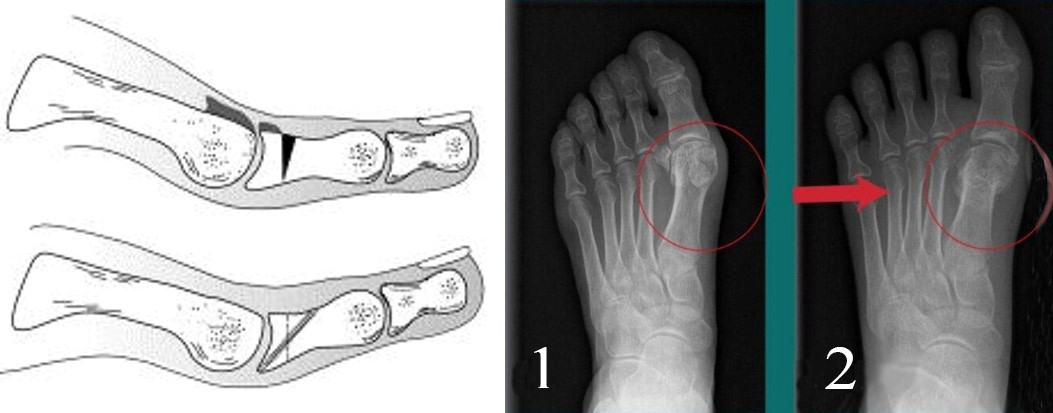

У далекому 1887 Девіс-Коллі вперше використовував термін Hallux limitus. З того часу були різні теорії про виникнення деформуючого остеоартрозу першого плюснефалангового суглоба. Nilsonne, в 1930 році вважав, що це захворювання є наслідком наявності занадто довгої першої плюсневої кістки, яка чинить тиск на суглобову поверхню основної фаланги. Викликано це нездатністю основи проксимальної фаланги проводити адекватне тильне згинання щодо першої плюсневої кістки. При рентгенологічному обстеженні пацієнтів було виявлено тильне зміщення головки 1 плюсневой кістки, наслідком чого є порушення біомеханіки руху в суглобі. Така особливість першої плюсневої кістки була названа metatarsus primus elevatus (піднята перша плюснева кістка). Kessel і Bonney також виявили, що у невеликому відсотку випадків розсікаючий остеохондрит головки першої плюсневої кістки веде до формування дегенеративних змін у суглобі з подальшим обмеженням тильного згинання.

Тильна клиноподібна остеотомія основної фаланги першого пальця або операція Моберга при Hallux Rigidus (ліворуч). Коригувальна вкорочуюча остеотомія, виконана черезшкірним методом (праворуч)

У пацієнтів похилого віку з вираженою патологією (3-4 стадія) з низькими функціональними запитами може бути використана резекційна артропластика або операція Келлера. Операція протипоказана у разі ригідної гіперекстензії першого пальця стопи, оскільки сама собою призводить до підвищеного ризику даної патології. Крім цього, призводить до значного ослаблення поштовху стопи і може призводити до метатарзалгії за рахунок навантаження головок інших плюсневих кісток.

Резекційна артропластика або операція Келлера при лікуванні ригідного першого пальця стопи